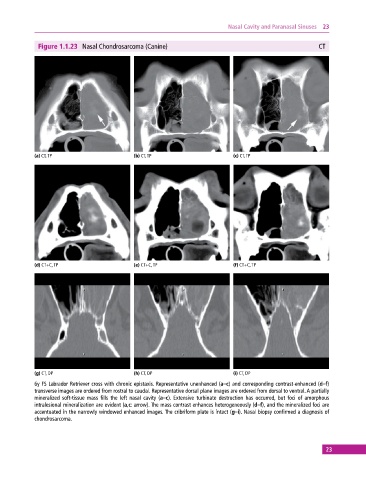

Figure 1.1.23 Nasal Chondrosarcoma (Canine) CT

(a) CT, TP (b) CT, TP (c) CT, TP

(d) CT+C, TP (e) CT+C, TP (f) CT+C, TP

(g) CT, DP (h) CT, DP (i) CT, DP

6y FS Labrador Retriever cross with chronic epistaxis. Representative unenhanced (a–c) and corresponding contrast‐enhanced (d–f)

transverse images are ordered from rostral to caudal. Representative dorsal plane images are ordered from dorsal to ventral. A partially

mineralized soft‐tissue mass fills the left nasal cavity (a–c). Extensive turbinate destruction has occurred, but foci of amorphous

intralesional mineralization are evident (a,c: arrow). The mass contrast enhances heterogeneously (d–f), and the mineralized foci are

accentuated in the narrowly windowed enhanced images. The cribriform plate is intact (g–i). Nasal biopsy confirmed a diagnosis of

chondrosarcoma.